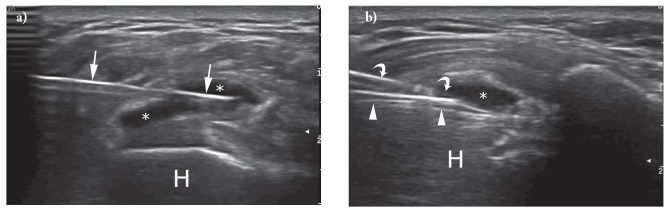

- Phân loại dựa trên siêu âm khác của Sconfienza và cộng sự:

- (i) vôi hóa cứng, tăng âm với bóng cản âm mạnh;

- (ii) vôi hóa mềm, tăng âm, gần như đẳng âm với gân, không có bóng âm; và

- (iii) vôi hóa dịch, giảm/không phản âm, không có bóng âm (Hình 4). Cách phân loại này chủ yếu liên quan đến ba loại viêm gân hóa chóp xoay khác nhau thường gặp ở những bệnh nhân trải qua các thủ thuật can thiệp.

Kỹ thuật:

Các phương pháp tiếp cận khác nhau đã được báo cáo trong các nghiên cứu gần đây và tất cả đều bao gồm việc sử dụng chất lỏng (thuốc tê cục bộ hoặc dung dịch muối) để hòa tan cặn canxi; một kim hoặc hai kim được sử dụng để tiêm và hút chất lỏng để hòa tan cặn canxi. Phương pháp sử dụng hai kim có thể hiệu quả hơn để điều trị các cặn cứng hơn, trong khi một kim có thể phù hợp trong điều trị vôi hóa dạng dịch.

Tóm tắt thủ thuật:

- Bệnh nhân nằm ngửa, vô trùng da và đầu dò siêu âm, thăm dò siêu âm thấy lắng đọng vôi hóa;

- tiêm một lượng nhỏ thuốc gây tê cục bộ (lên đến 10 ml lidocain) vào bao hoạt dịch dưới mỏm cùng vai và gần vùng vôi hóa. Nếu sử dụng hai kim, kim đầu tiên sẽ được đưa vào phần thấp nhất của phần vôi hóa với mặt vát của kim hướng về phía đầu dò, trong khi kim thứ hai được đưa vào phần vôi hóa song song và nông so với kim thứ nhất, với mặt vát đối diện với kim thứ nhất để tạo vòng hút rửa.

- Bơm dung dịch nước muối vào qua kim thứ nhất để hoà tan lắng đọng vôi hoá, và hút dung dịch hoà tan ra với kim thứ hai, cho đến khi thấy bên trong rỗng hoàn toàn. Nếu chỉ sử dụng một kim tiêm, quy trình bơm rửa hút này được thực hiện tương tự, với bơm nước muối vào và hút dịch hoà tan ra trong cùng một ống tiêm. (Hình 5)